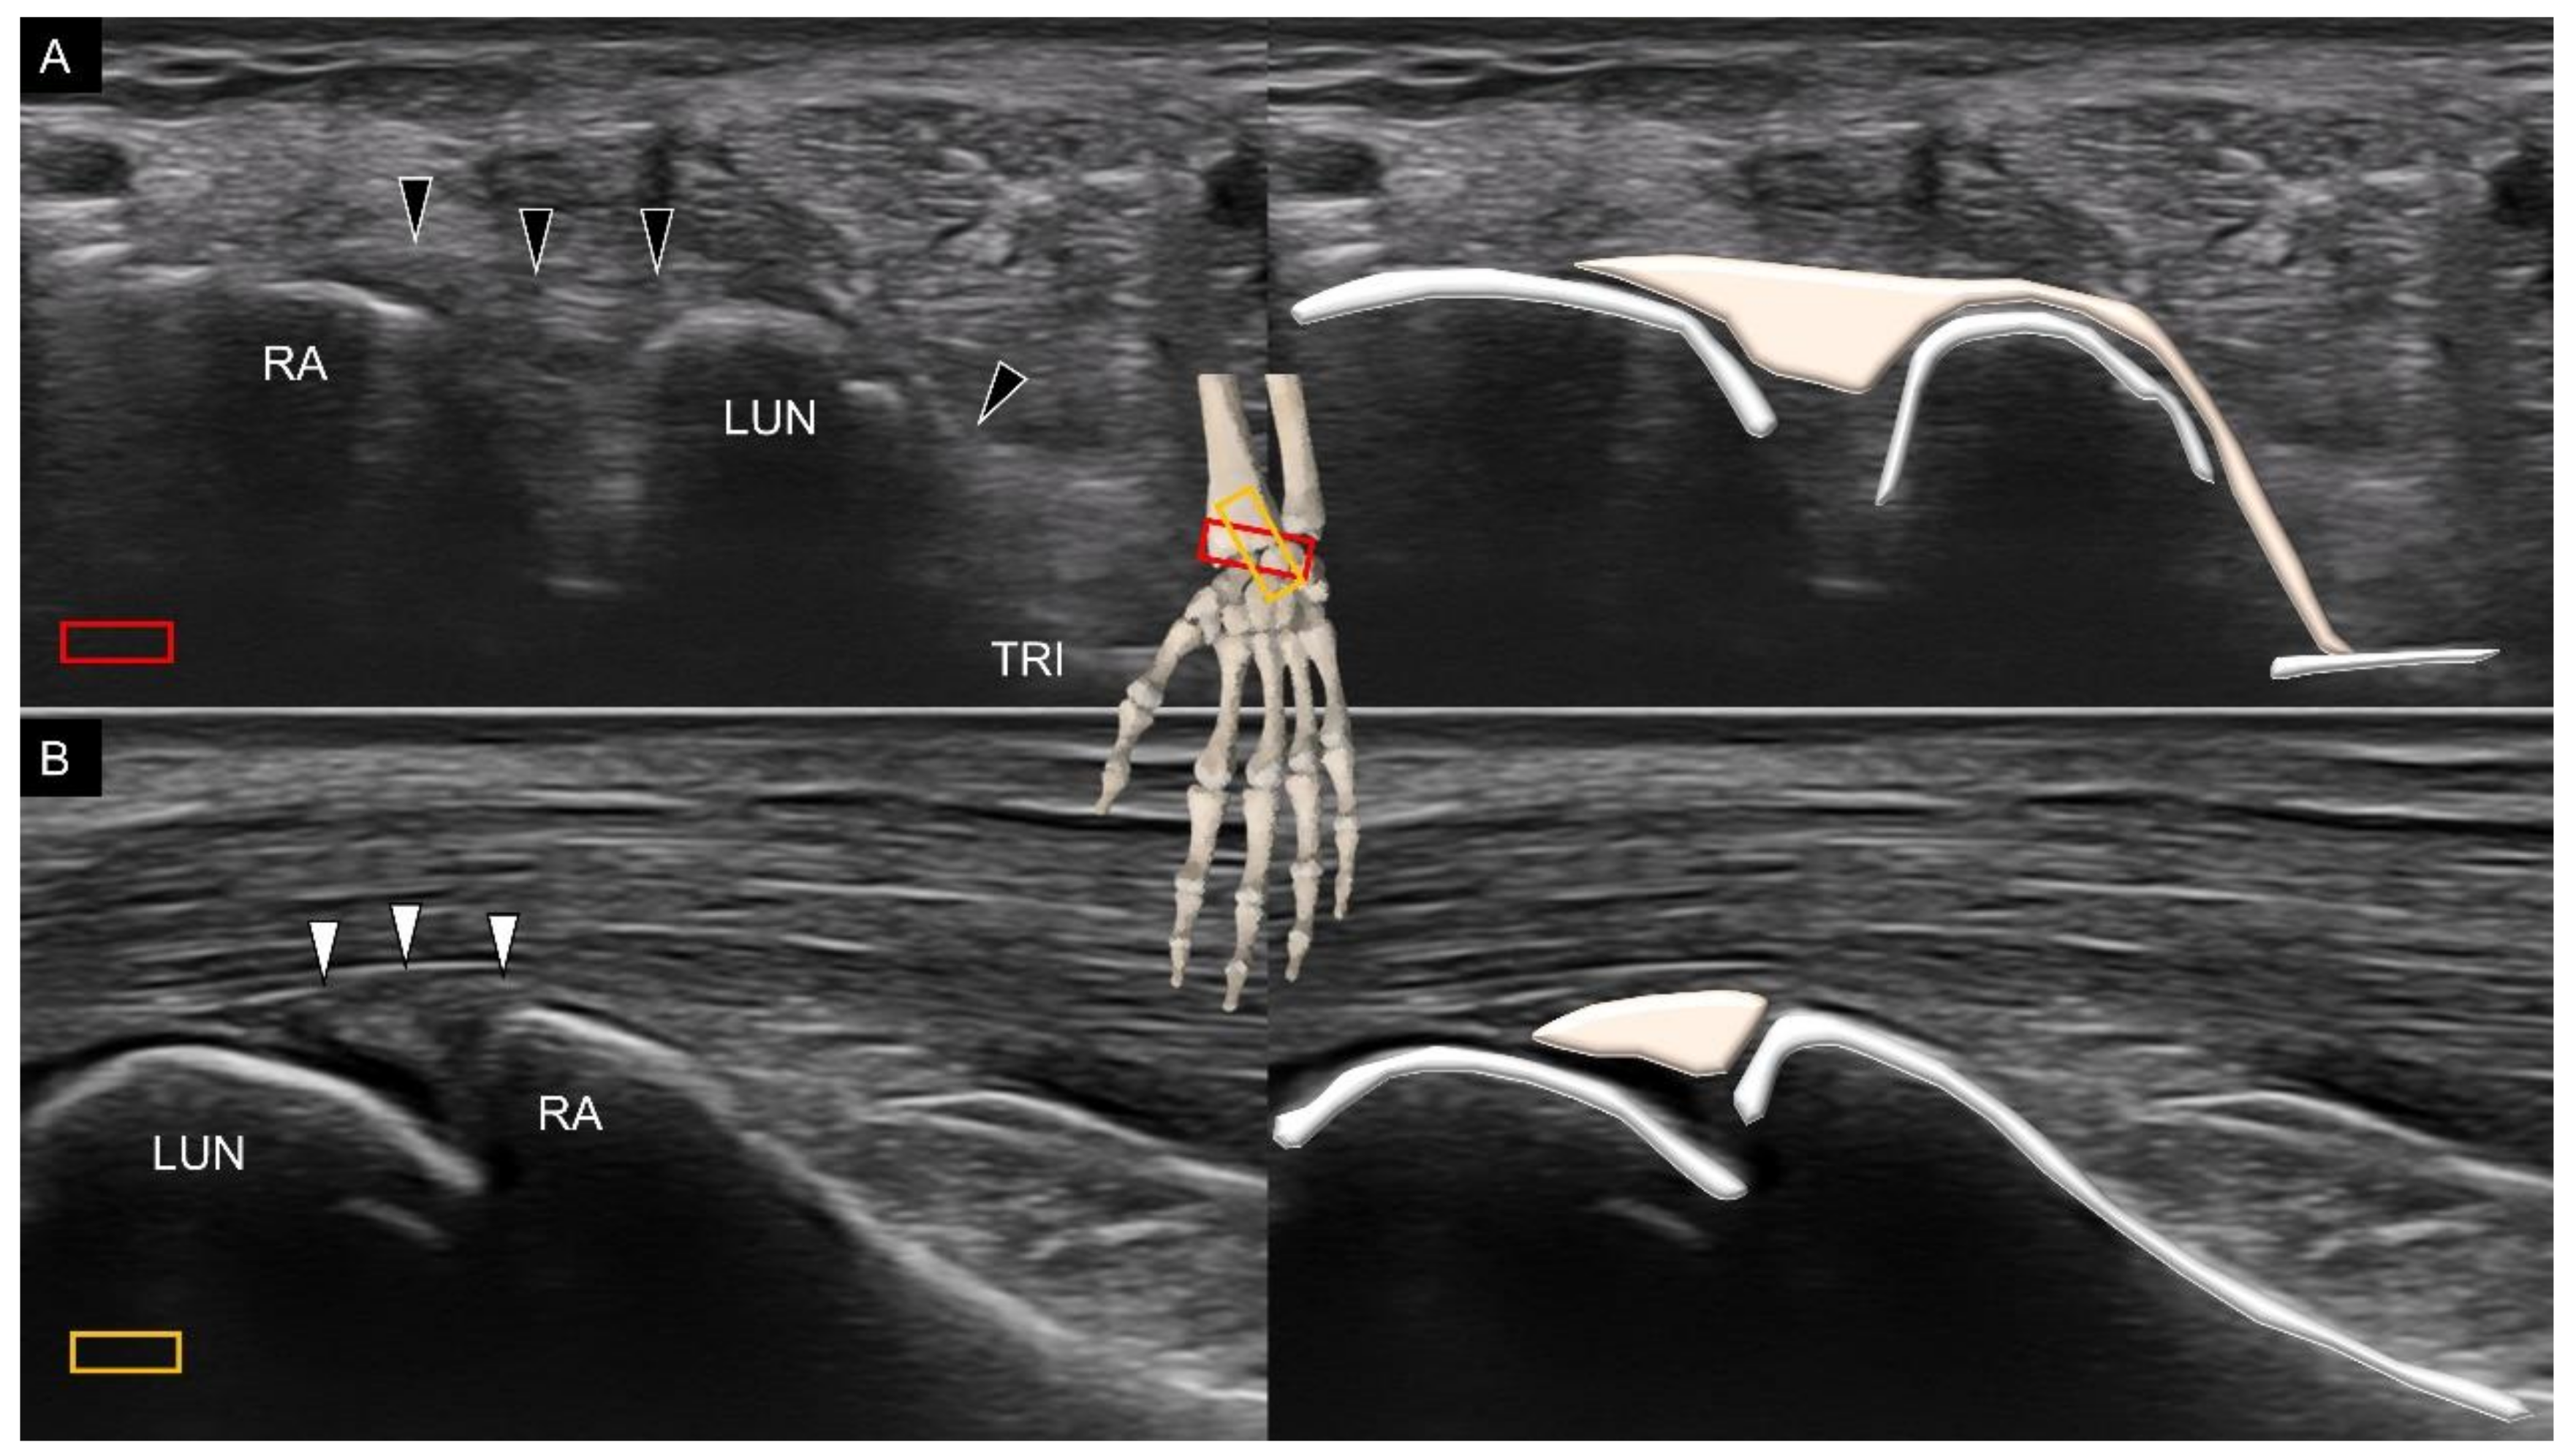

2. Sonoanatomy of Carpal Bones

3.2. Attachment to the Lunate

3.3. Attachment to the Triquetrum